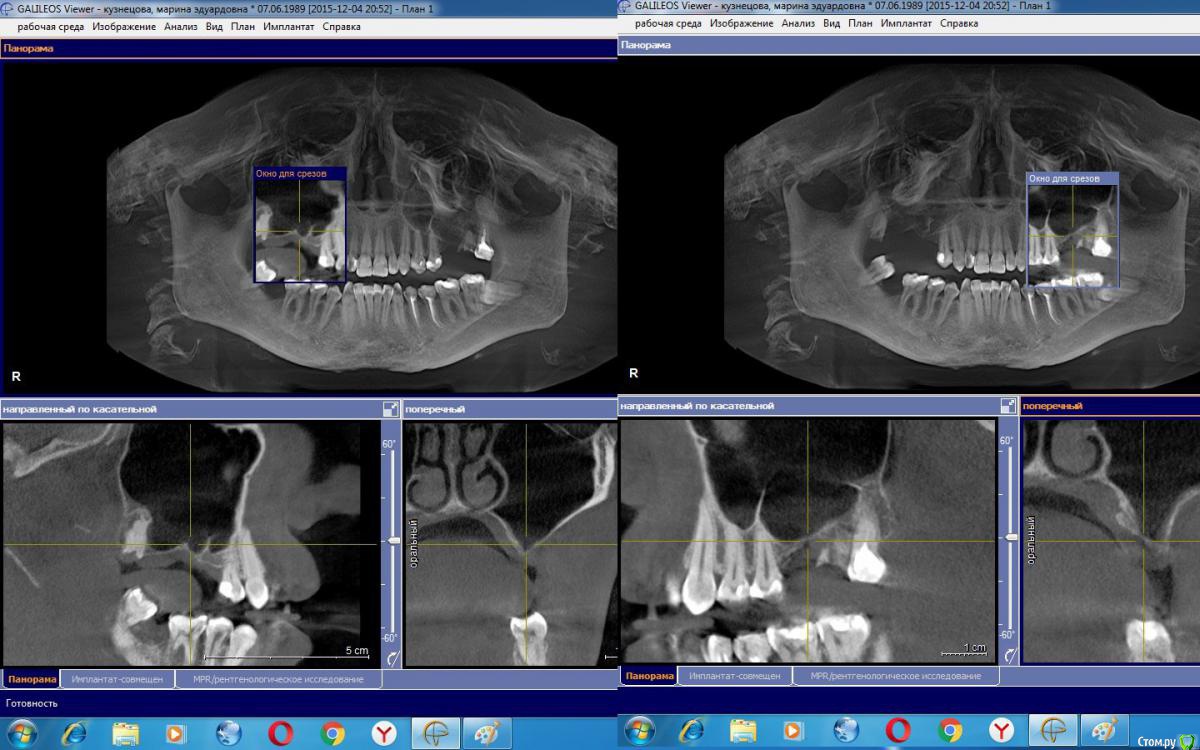

Lilmur Опубликовано 14 сентября, 2016 Поделиться Опубликовано 14 сентября, 2016 Решила заняться зубами. Обратилась в стоматологическую клинику. Но ввиду отсутствия зубов, и как мне объяснили, атрофии кости, предложили синуслифтинг с 2х сторон. Моей особенностью является то, что ранее были перфорации пазухи во время удаления зуба слева и справа. Первая операция была под наркозом 5.02.16, планировался двухсторонний синус лифт, взятие своей кости справа на нижней челюсти. Измельченная кость смешивалась с cerabone и центрифугированной плазмой. Окно закрывалось jason мембраной. Слева все сделали, но справа, в пазухе доктор обнаружил мукоцеле с гнойным содержимым, поэтому синуслифтинг пришлось отменить и подождать. Особо жалоб не было, разве что были ощущения стянутости и тяжести с 2хз сторон. 13.02.16 повторное КТ- имеются явления синусита. Но вероятно, я на тот момент болела простудой. Через несколько месяцев (около 2-3 мес) после первой операции попробовали снова синуслифтинг справа. И снова не получилось. Со слов врача, кость очень тонкая, по консистенции даже мягкая (!!!), и есть незаживающая перфорация в кости. Операцию еще раз отложили. Вот последнее КТ на котором видна очень тонкая кость справа и места перфораций. По рекомендации лечащего врача была на консультации ЧЛХ в 1ом меде у другого врача, (назову его X) который предложил повторный синус с подвздошной костью. Мой лечащий врач очень хвалит Х , но я хочу продолжить лечение у своего врача и брать кость с угла челюсти. Ни в коем случае не виню своего врача в первых двух попытках, котрые ни к чему не привели, сама все вижу по снимкам. В начале ноября решили попробовать ещё раз. Хотелось бы послушать мнения других специалистов. Видите ли вы какую-то положительную динамику, что можно сказать вообще по этими снимкам.Буду благодарна за любые мнения и комментарии. Заранее спасибо! Ссылка на комментарий

red_butler Опубликовано 14 сентября, 2016 Поделиться Опубликовано 14 сентября, 2016 Есть определенные сложности связанные со строением синусов, фрагмент корня слева. Но это все решаемо. Какой либо необходимости в использовании аутокости, тем более из вне ротовых источников не увидел. 6 Ссылка на комментарий

колесников Опубликовано 14 сентября, 2016 Поделиться Опубликовано 14 сентября, 2016 Перегородки в правой пазухе усложняют отслаивание мембраны. Есть методы и при таких случаях. Ауто кость хотели брать видимо для того,что бы восстановить гребень слева. К содержимому левой пазухи есть вопросы,по данным срезам сложно сказать определённо. 1 Ссылка на комментарий

Bier Опубликовано 15 сентября, 2016 Поделиться Опубликовано 15 сентября, 2016 так на этом КТ синуслифтинг не сделан ни с одной ни с другой стороны... Есть новая КТ? выкладывайте ее целиком. Ссылка на комментарий

Alejandro Опубликовано 16 сентября, 2016 Поделиться Опубликовано 16 сентября, 2016 Тоже не вижу следов операции. Нужно свежее кт Ссылка на комментарий